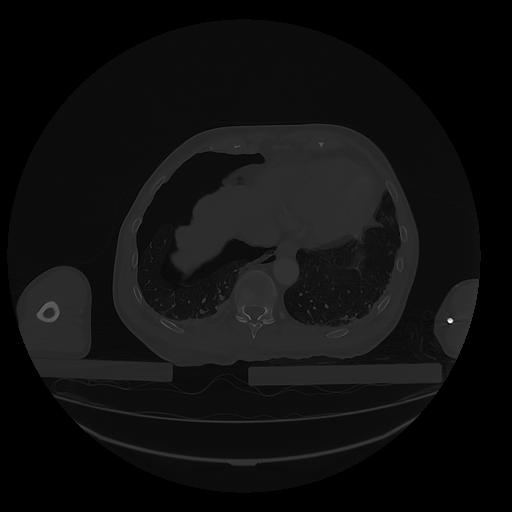

31 PULMON,CE,Vol,1.0,PULMON,,